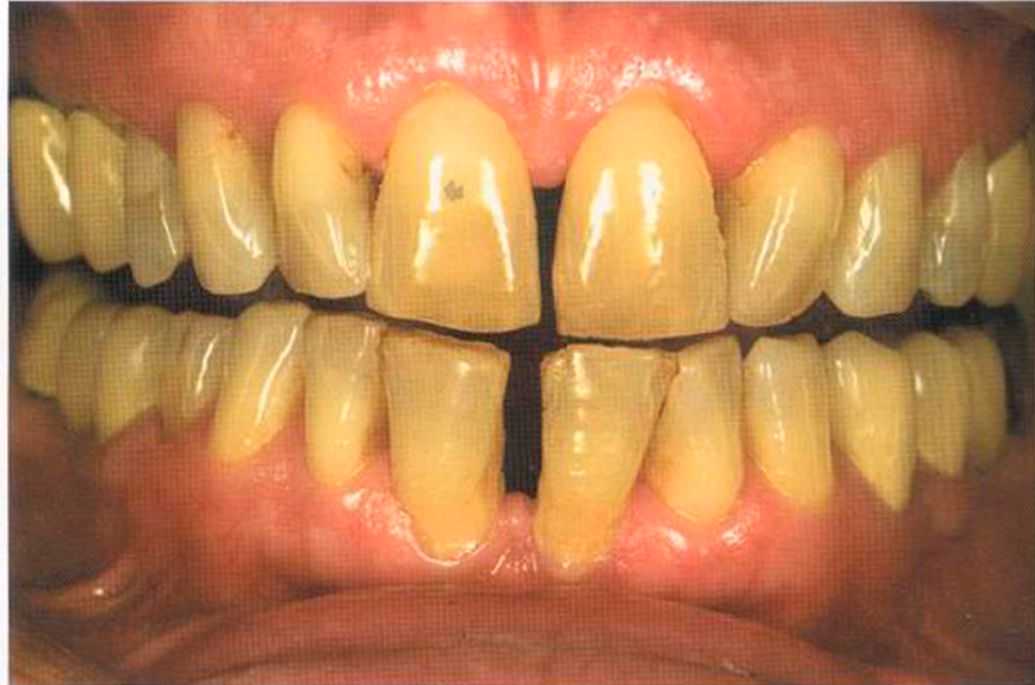

Вспомним, как все начиналось.

Первое лечение проходию много лет назад у другого доктора. Со временем ос те пи / ка уху дин ьась, особенно в пришеечной области. Этот пациент хотел новые коронки в области 12 и 22, по сомневсься, нас кол ько хорошо они будут выглядеть.

Результат с использованием In-Ceram развеял все сомнения, и решение об изготовлении коронки на другой боковой резец не заставило себя долго ждать.

После того как мы определит цвет зуба, решено быо сначсьа изготовить одну коронку.